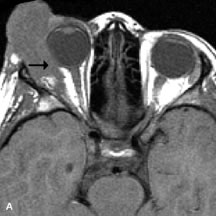

Pleomorphic adenomas demonstrate long T1 and T2 signal characteristics. They may show heterogeneity on T2-weighted images74 and moderate to marked enhancement with contrast.75 Signal characteristics of adenoid cystic carcinoma include hypointensity to fat on T1-weighted images, hyperintensity to fat with increased T2 weighting, and isointensity to fat on proton density-weighted studies (Fig. 23).31,75 Secondary bony alterations of the lacrimal fossa associated with lacrimal gland tumors, such as remodeling (benign mixed tumor) or destruction (adenoid cystic carcinoma), are seen indirectly on MR images; however, bone windows on CT scans provide better delineation of these changes. In contrast to the round or globular appearance of benign or malignant epithelial tumors of the lacrimal gland, lymphoproliferative tumors usually appear to be molding or draping onto the globe and the surrounding bony orbit.

Fig. 23. A. T2-weighted and (B and C) postcontrast fat-suppressed T1-weighted MR scans demonstrate an infiltrative lacrimal region mass than invades the lateral rectus muscle (arrows). This highly cellular lesion is seen to have a very hypointense appearance on the T2-weighted scan.